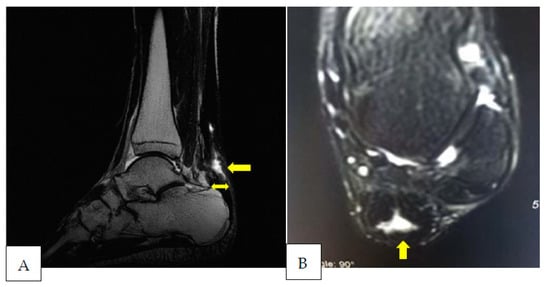

2. Case Presentation